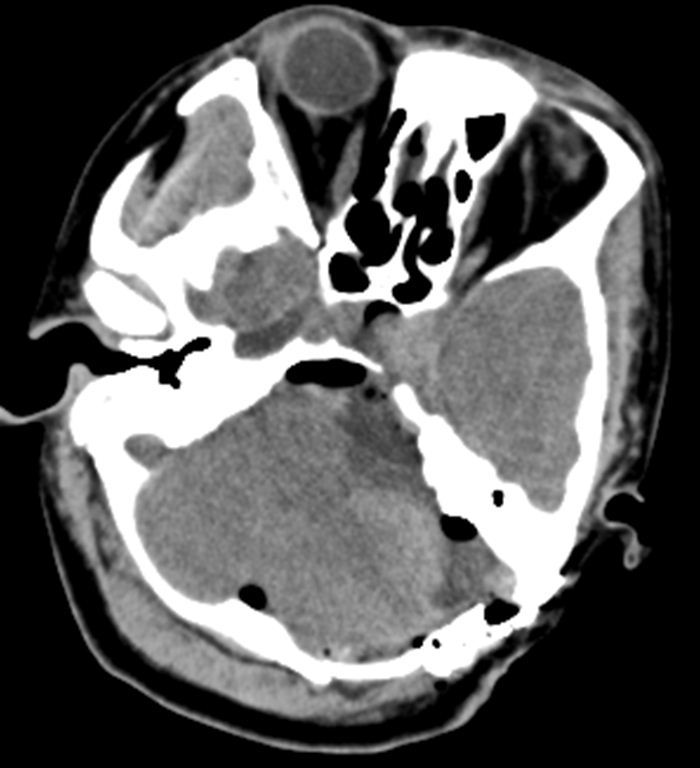

术后即刻头颅CT检查